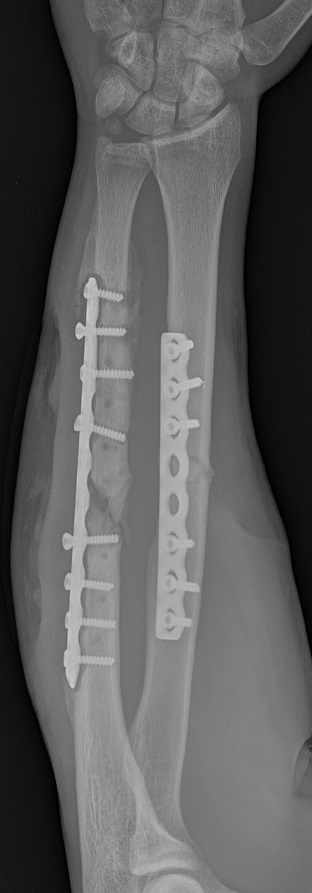

- открытый оскольчатый перелом средней трети левого предплечья с повреждением лучевого нерва- Выполнен остеосинтез пластинами- Миграция осколка локтевой кости- Реостеосинтез локтевой кости- Проявилось нагноение пластины, хронический посттравматический остеомелит, образовался ложный сустав- На левом предплечье три действующих свища.

Пациент 28 лет. С момента травмы до снимка прошло 6 мес.В этот промежуток времени выполнялись перевязки на месте свищей, сильных болевых ощущений не было. Однако примерно 3 дня назад появилось воспаление в области перелома, поднялась температура, появились сильные боли в предплечье.Вопросы:- На сколько время в данной ситуации играет против меня, с какой скоростью усугубляется ситуация.- Осложнения в виде повышения температуры и усиления болевых ощущений в порядке вещей в данном случае ?На данный момент показано удаление пластины, и последующий реостеосинтез аппаратом илизарова, однако я нахожусь в очереди, и по прогнозам смогу лечь на операцию не раньше, чем через 3 месяца. Просто хотелось бы услышать мнение профессионалов.

Мнение - о чем конкретно? Все, что планируется, вполне в рамках принятых представлений. Инфекция требует удаления нестабильного "железа", санации очага путем повторных хирургических обработок. Да, целесообразен остеосинтез аппаратом. Какой будет в итоге костный дефект - неизвестно. Соответственно, как и чем его замещать, пока обсуждать невозможно.